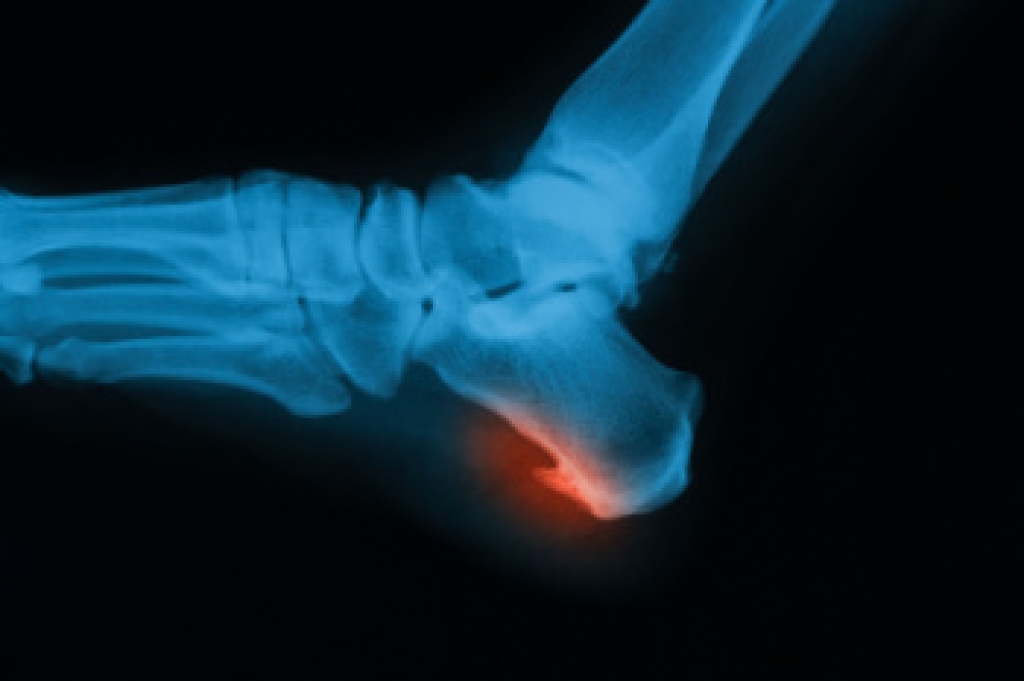

Explaining Heel Spur Surgery

Heel spur surgery is considered when a bony growth on the heel bone continues to cause pain despite other forms of care. These spurs form when repeated strain on the foot leads to calcium buildup along the bottom or back of the heel bone, or calcaneus. Although not all heel spurs cause pain, in some cases they can create pressure and irritation with each step. Surgery removes the excess bone and reduces tension on nearby tissues, including the plantar fascia on the sole of the foot or the Achilles tendon at the back of the ankle. A podiatrist will examine the source of the pain, review imaging, and decide whether the spur on the bottom of the heel or near the tendon attachment needs to be removed. Recovery takes time as the foot heals and strength returns. If you have developed a heel spur that is causing pain, it is suggested that you make an appointment with a podiatrist for a diagnosis and treatment.

Heel spurs are formed by calcium deposits on the back of the foot where the heel is. This can also be caused by small fragments of bone breaking off one section of the foot, attaching onto the back of the foot. Heel spurs can also be bone growth on the back of the foot and may grow in the direction of the arch of the foot.

Older individuals usually suffer from heel spurs and pain sometimes intensifies with age. One of the main condition's spurs are related to is plantar fasciitis.

The pain associated with spurs is often because of weight placed on the feet. When someone is walking, their entire weight is concentrated on the feet. Bone spurs then have the tendency to affect other bones and tissues around the foot. As the pain continues, the feet will become tender and sensitive over time.

There are many ways to treat heel spurs. If one is suffering from heel spurs in conjunction with pain, there are several methods for healing. Medication, surgery, and herbal care are some options.